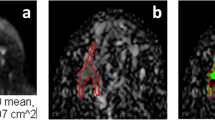

A dataset of 402 malignant and 257 benign lesions was identified. Two radiologists assigned the KS. If a lesion with KS > 4 had ADC > 1.4 × 10−3 mm2/s, the KS was reduced by 4 to become KS+. In order to consider the full spectrum of ADC as a continuous variable, the KS and ADC values were used to train diagnostic models using 5 ML algorithms. The performance was evaluated using the ROC analysis, compared by the DeLong test. The sensitivity, specificity, and accuracy achieved using the threshold of KS > 4, KS+ > 4, and ADC ≤ 1.4 × 10−3 mm2/s were obtained and compared by the McNemar test.

The ROC curves of KS, KS+, and all ML models had comparable AUC in the range of 0.883–0.921, significantly higher than that of ADC (0.837, p < 0.0001). The KS had sensitivity = 97.3% and specificity = 59.1%; and the KS+ had sensitivity = 95.5% with significantly improved specificity to 68.5% (p < 0.0001). However, when setting at the same sensitivity of 97.3%, KS+ could not improve specificity. In ML analysis, the logistic regression model had the best performance. At sensitivity = 97.3% and specificity = 65.3%, i.e., compared to KS, 16 false-positives may be avoided without affecting true cancer diagnosis (p = 0.0015).